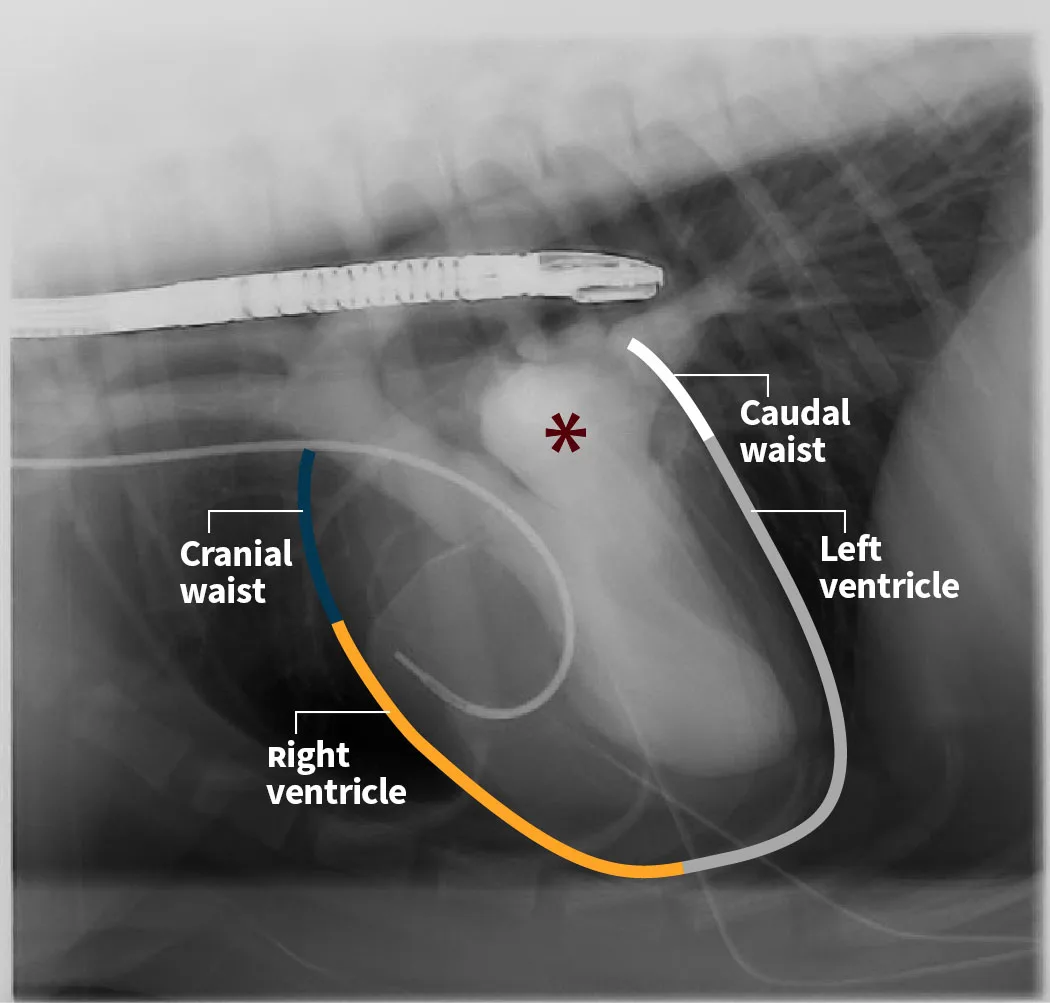

The cardiac silhouette should be evaluated systematically. Using the clockface analogy when evaluating DV or VD projections, the apex of the heart is located at ≈5 o’clock, and the right ventricle is in the region between 5 and 6 o’clock to 9 o’clock, followed by the right atrium, aortic arch, main pulmonary artery (MPA), left auricle, and left ventricle (Figure 4). A similar approach can be followed when evaluating the heart in a lateral projection. The terms cranial and caudal waist or borders are used to describe regions of the cardiac silhouette (Figure 5). Changes within particular regions can indicate which structure is likely abnormal and highlight potential underlying disease processes.

FIGURE 5 Levophase of a right ventricular outflow tract angiogram in a dog undergoing cardiac intervention. The pulmonary veins, left atrial (asterisk) and ventricular lumens, and ascending and descending intrathoracic aorta can be seen. The cranial and caudal waists (normal in this patient) are highlighted in blue and white, respectively. The great vessels, right atrium, and right auricle are located near the region of the cranial waist, whereas the left atrium and pulmonary veins are located near the region of the caudal waist. The orange and gray lines outline the regions of the right and left ventricles, respectively. An angiographic catheter is in the right ventricular outflow tract, transthoracic pacing patches have been applied, and a transesophageal echocardiography probe is positioned dorsally to the left atrium. Illustration courtesy of Jose Narvaez Perez